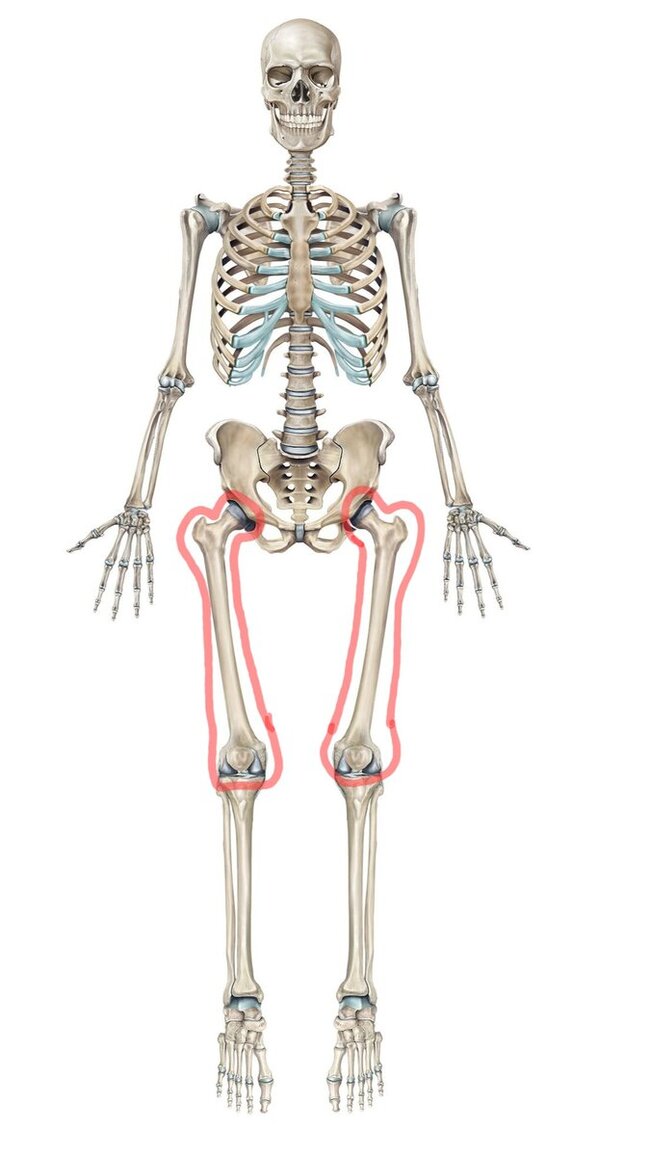

Вот большеберцовые кости в скелете.